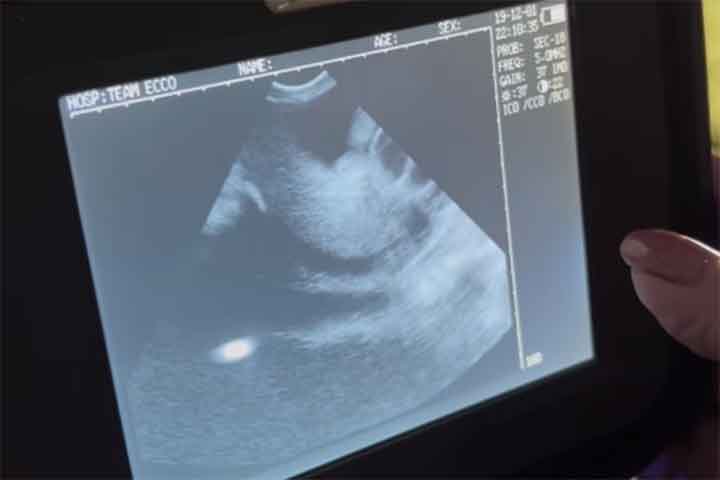

Independente: Arraia ‘engravida’ sem ter contato com macho